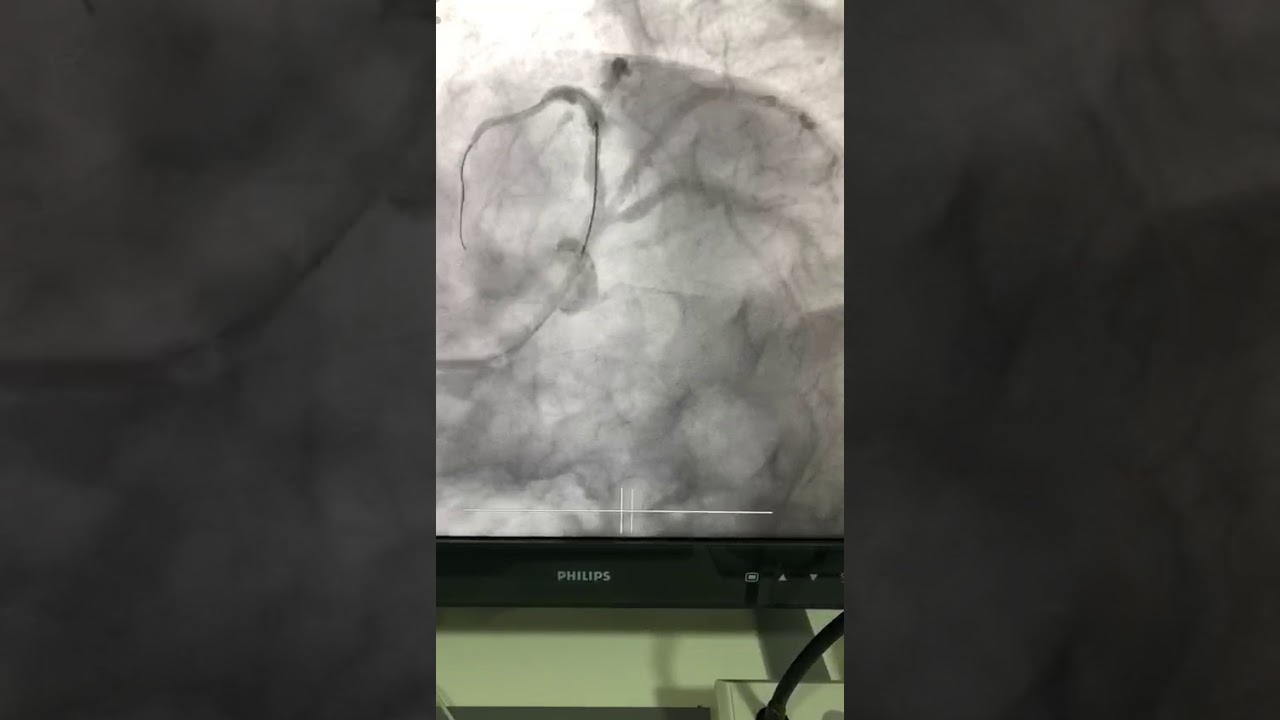

Realicé mi formación como médico general en la Universidad Autónoma de Veracruz Villa Rica, posteriormente la especialidad en medicina interna durante dos años en centro medico nacional Adolfo Ruiz Cortinez UMAE 14 en Veracruz, recibiendo en el primer año el reconocimiento por excelencia académica y en el segundo año reconocimiento al mejor promedio de mi generación. Realicé la subespecialidad en Cardiología clínica en el Centro Médico Nacional “La Raza”, en la Ciudad de México siendo jefe de residentes en el último año de la residencia médica, durante el tiempo la sede recibió el premio a la mejor cede de formadores de cardiología 2012-2013 premio otorgado por Dr. Enrique Graube (en ese entonces Director de medicina UNAM). Entre mis actividades asistenciales y conferencias, he presentado trabajos libres a nivel internacional (congreso de falla cardiaca lisboa 2013, Congreso mundial de cardiologia 2016, 2018 en AHA) ganador del premio internacional “la imagen más bella en cardiología, sociedad europea cardiologia España 2013”, así mismo presentación de más de 35 articulos publicados en revistas indexadas, soy miembro de la sociedad mexicana de cardiología no. 2076, asociación mexicana de cardiología, Fellow in training de la American collegue of cardiology capítulo México. Miembro de la sociedad europea de cardiología ESC ID 509395. Médico adscrito en el centro médico nacional la Raza, fui profesor adjunto del curso de cardiología en el mismo centro y sindal en el exámen de certificación de cardiología clínica de la sociedad mexicana de cardiología. Desde el 2016-2018 realicé curso de alta especialidad en electrofisiología cardiaca y estimulación cardiaca , realizando cursos fuera del país para especialización en técnicas avanzadas de ablación de arritmias, actualmente me encuentro realizando en el segundo año de la maestría en Dirección y Gestión de Instituciones de salud y Especialidad en Gestión de la Salud y Bienestar Corporativo